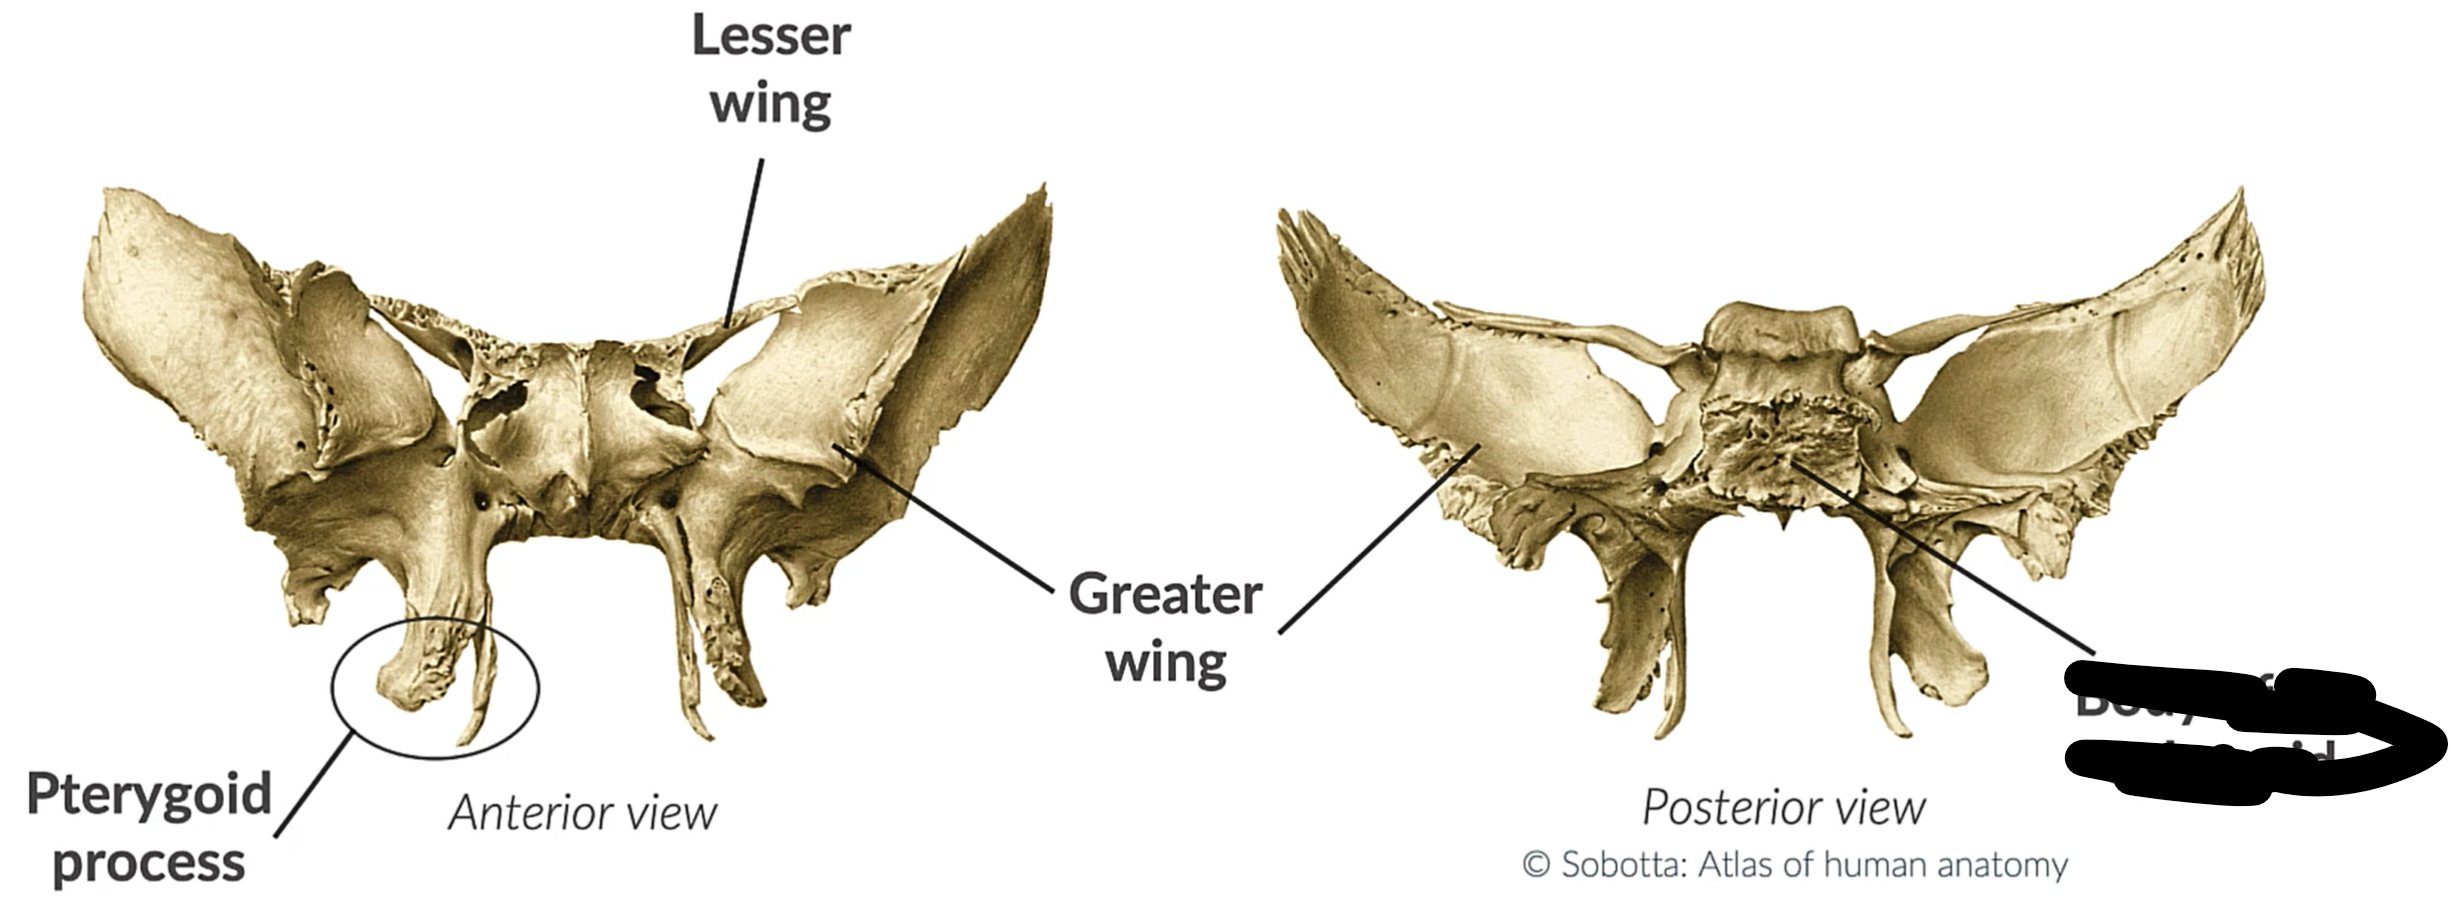

What bone is this?

Sphenoid bone

Lesser wing

Greater wing

Pterygoid process

Body sphenoid bone